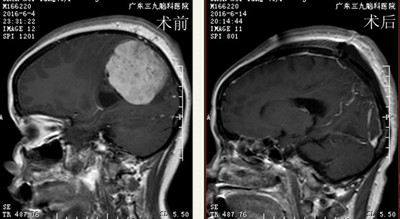

▲术前术后MR矢状位对比